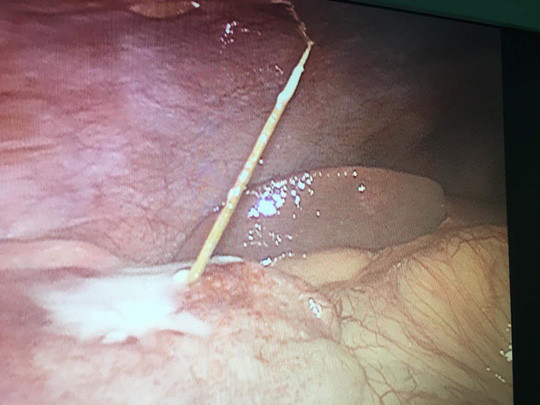

CT scan bụng cho thấy hình ảnh dày thành 1 quai ruột non ở hông phải, thành ruột dày 1 cm, dài 8 cm. Chẩn đoán trước mổ là viêm ruột thừa cấp. Ê kíp phẫu thuật gồm BS.CKII Trương Thanh Sơn và ThS-BS Lê Quang Huy, phẫu thuật nội soi ổ bụng thấy cây tăm xỉa răng dài 5 cm đâm thủng hồi tràng. "Chúng tôi lấy dị vật ra ngoài ổ bụng, khâu lại chỗ thủng ruột non qua nội soi với chỉ tan. Ngày hậu phẫu thứ nhất bệnh nhân tỉnh, vết mổ đau ít, chưa trung tiện. Bệnh nhân không nhớ đã nuốt tăm xỉa răng"-đại diện của Bệnh viện Đa khoa Trung ương Cần Thơ cho biết.